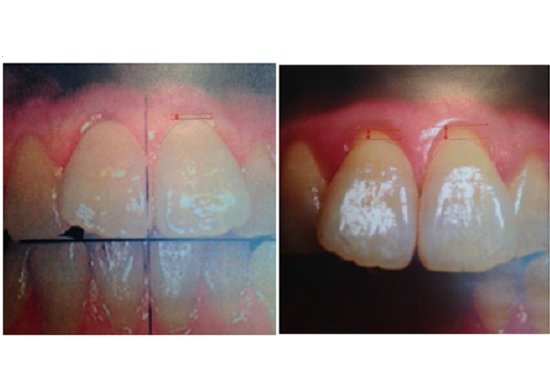

最後に私が診させてもらっている患者さんの症例を紹介します。初診が2001年ですから、15年経過しています。左が01年撮影、右が16年撮影のものです。

15年の間に上の前歯の歯肉が明らかに退縮しています。つまり、歯周組織の破壊が起こっているのです。この患者さんは欠かさず定期健診を含め、年に4回以上の受診をされています。しかし、この15年の間に上の前歯が腫れたりして、いわゆる歯周処置を行った記録はカルテにはありません。また、現時点(右の写真)でも、治療を要する炎症像はありません。今まで臨床に携わってきて、いつも違和感のある現象でした。

しかし、歯周炎を細菌性の炎症のみが原因として捉えずに、歯周炎関連線維芽細胞のような歯周炎の原因細胞が存在すると考えると、このような現象にかなり違和感がなくなります。